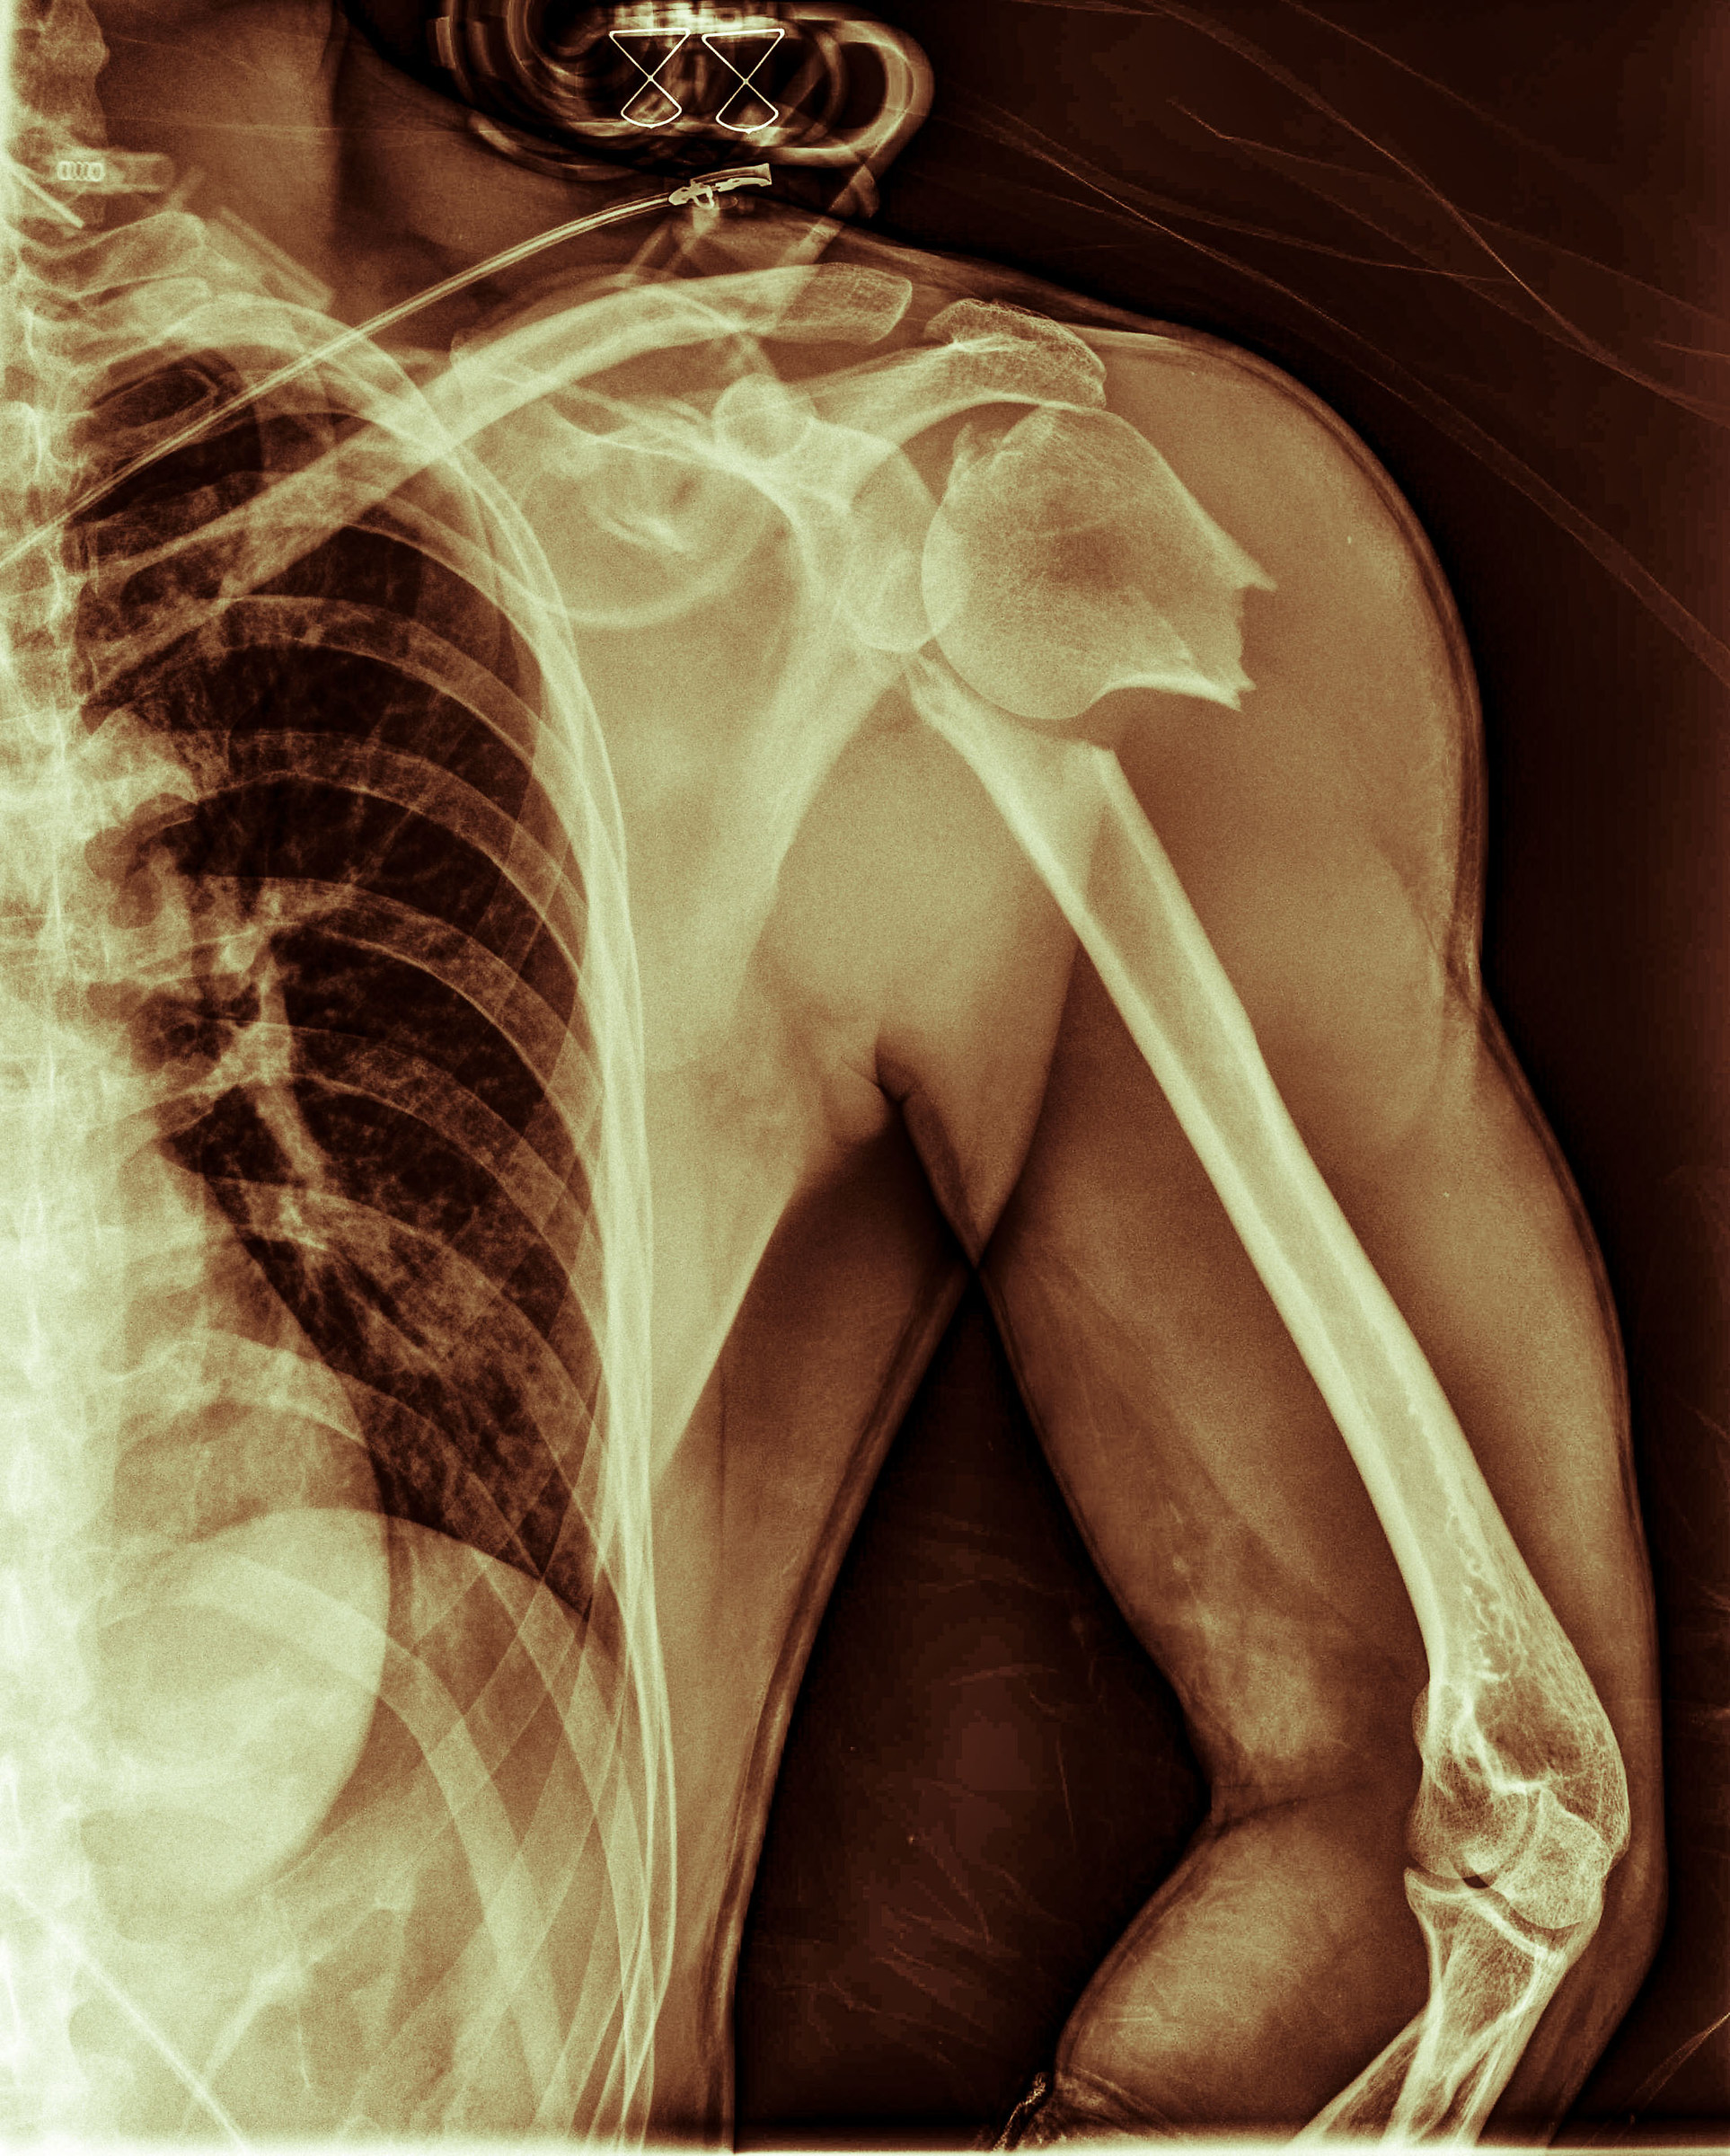

You made a nice damage .... now everything ok? Still great idea Mat Ti sei fatto un bel danno.... ora tutto ok? Comunque ottima idea Mat |

Ciao, grazie! Sul danno ci sto lavorando: comincio a camminare di nuovo (mi sono rotto anche il ginocchio, ma è meno fotogenico!), ho ripreso a nuotare... ma ci vorranno ancora mesi e mesi di lavoro. grazie davvero del passaggio, mi ha fatto piacere Lore

Bye thank you! The damage I'm working: I start to walk again (I even broke my knee, but it's less photogenic!), I started to swim ... but it will take months and months of work.

Vacca schifa che macello che ti sei fatto alla spalla

Cow slaughter disgusted that you've had to shoulder :-( Vacca schifa che macello che ti sei fatto alla spalla |

Eh sì! E pensa che stavo solo andando a lavoro in bicicletta, niente di particolarmente stravagante! :)

Oh yeah! And I think that I was just going to work by bike, nothing particularly extravagant! :) Eh sì! E pensa che stavo solo andando a lavoro in bicicletta, niente di particolarmente stravagante! :) |

Mi dispiace per la caduta in bici.. Comunque hai avuto un'idea geniale nel realizzare questa immagine, e l'hai realizzata alla grande, complimenti Un saluto Rossano

I'm sorry for the fall in bike .. Anyway you had a brilliant idea to realize this, and have made great, congratulations A greeting Rossano Mi dispiace per la caduta in bici.. Comunque hai avuto un'idea geniale nel realizzare questa immagine, e l'hai realizzata alla grande, complimenti Un saluto Rossano |

Mi accodo ai complimenti. Questo è come trasformare piombo in oro.

I stepping stone to compliments. This is how to turn lead into gold. Mi accodo ai complimenti. Questo è come trasformare piombo in oro. |

Se lo merita tutto il complimento. In un certo senso sei un body artist Ti auguro un buon recupero. Anch'io vado al lavoro in bici... sperem.

He deserves all the praise. In a sense you are a body artist ;-) I wish you a good recovery. I'm going to work by bike ... sperem. Se lo merita tutto il complimento. In un certo senso sei un body artist Ti auguro un buon recupero. Anch'io vado al lavoro in bici... sperem. |